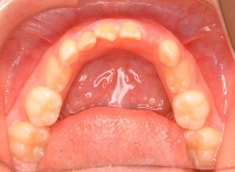

治療開始時